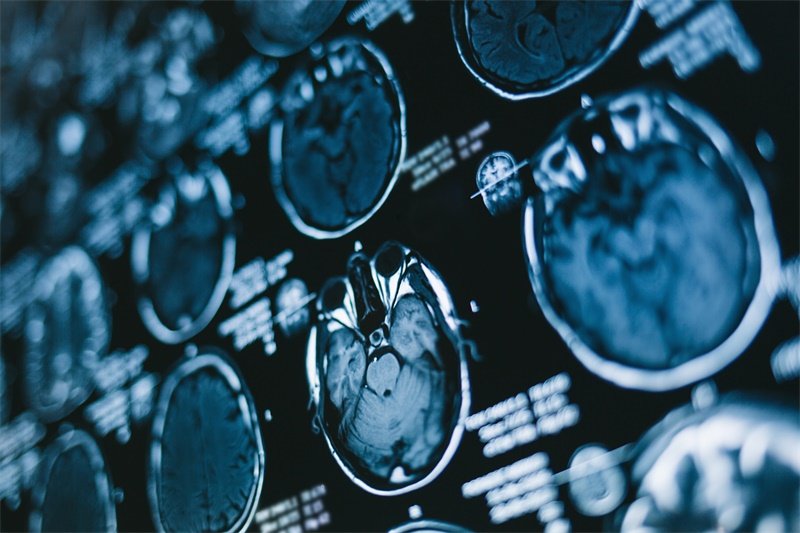

核磁共振成像(MRI)是常用的检查手段,可以清晰地显示脊髓和周围结构的状态。通过MRI,医生可以了解占位的性质、范围以及对周围结构的压迫情况。

此外,计算机断层扫描(CT)也常用于评估脊柱的骨骼结构,帮助医生解析肿瘤性质及定位。